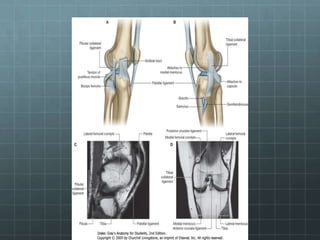

Ligamen pada sendi dapat dibagi dua yaitu

ligamen intracapsular dan extracapsular.

Ligamen intracapsular adalah ligamen yang

terdapat di dalam capsula articularis tapi tidak

di dalam cavum synovial (Ligamentum

Cruciatum Anterior dan Posterior).

Ligamen extracapsular adalah ligamen yang

terdapat di luar capsula articularis.

Anatomi

Genu

Meniskus

Lig. Cruciatum

Bursa

Ligament